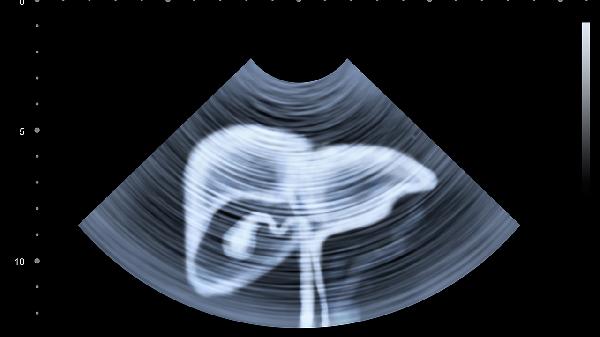

肝囊腫與肝癌在B超檢查中的區(qū)別主要體現(xiàn)在形態(tài)特征、回聲表現(xiàn)、血流信號(hào)等方面。肝囊腫多為圓形或橢圓形無(wú)回聲區(qū),邊界清晰;肝癌則表現(xiàn)為不規(guī)則低回聲或混合回聲團(tuán)塊,邊界模糊且可能伴有血流信號(hào)異常。建議發(fā)現(xiàn)異常影像時(shí)及時(shí)就醫(yī)明確診斷。

肝囊腫在B超下通常呈現(xiàn)為單發(fā)或多發(fā)的圓形無(wú)回聲區(qū),囊壁薄而光滑,后方回聲增強(qiáng),內(nèi)部無(wú)血流信號(hào)。這種表現(xiàn)與肝臟內(nèi)充滿液體的囊性結(jié)構(gòu)特征一致,多數(shù)為先天性或退行性改變,生長(zhǎng)緩慢且極少惡變。部分體積較大的囊腫可能壓迫癥狀,但通常不會(huì)引起肝功能異常。

肝癌的B超影像多顯示為邊界不清的低回聲或混合回聲團(tuán)塊,內(nèi)部回聲不均勻,可能出現(xiàn)"暈環(huán)征"或"鑲嵌征"等惡性腫瘤特征性表現(xiàn)。彩色多普勒檢查常可觀察到豐富紊亂的血流信號(hào),部分病例伴有門靜脈癌栓形成。肝癌病灶通常進(jìn)展較快,可能伴隨甲胎蛋白升高、消瘦等全身癥狀,需要結(jié)合增強(qiáng)CT或病理檢查確診。